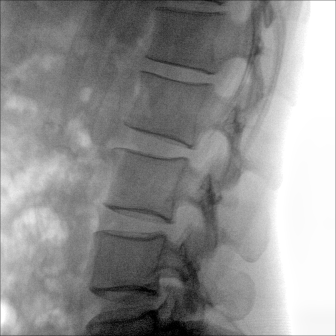

大尺寸動態(tài)平板探測器,高DQE、低噪聲、圖像清晰。采用多分辨率圖像增強處理技術(shù),不同部位不同圖像處理算法,滿足客戶多樣化的需求。

采用智能變頻脈沖透視技術(shù),優(yōu)化圖像質(zhì)量的同時降低輻射劑量,呵護(hù)醫(yī)患健康